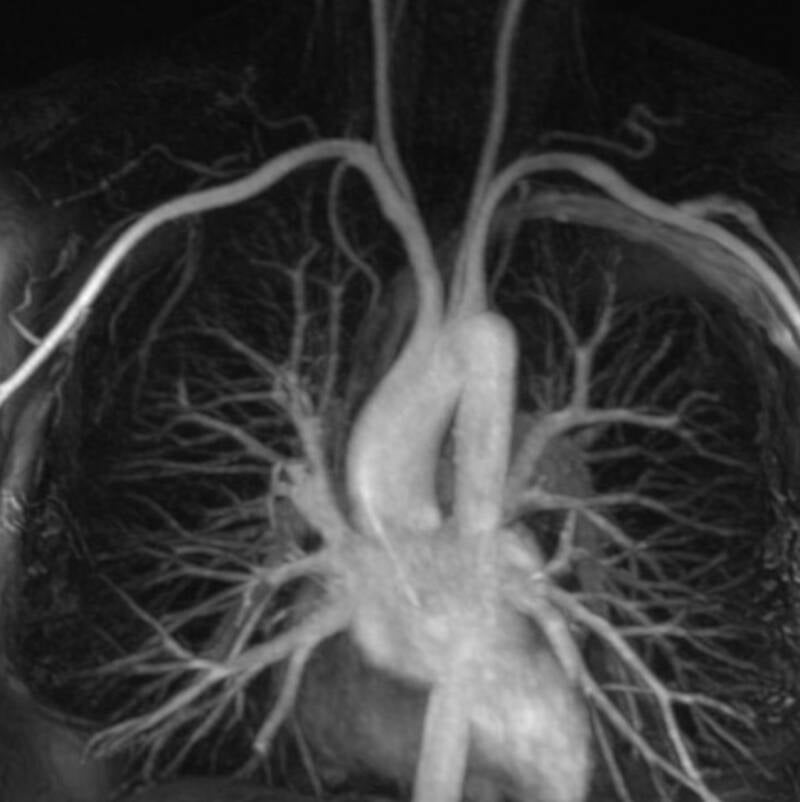

Anhand eines Angio MRT lassen sich in Provokationsstellung mit erhobenen Armen (rote Pfeile) in einigen Fällen Gefässbeeinträchtigungen nachweisen bei in Ruhe normalen Flussbedingungen. Flussunregelmässigkeiten lassen sich auch teilweise von angiologischer Seite mittels Ultraschall nachweisen.